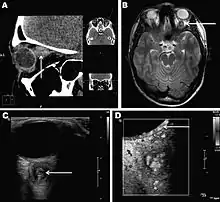

Infections in humans[3] usually manifest as a single subcutaneous nodule, which is caused by a macrofilaria that is trapped by the immune system. Subcutaneous migration of the worm may result in local swellings with changing localization. In addition, rare cases of organ manifestation have been reported, affecting the lung, male genitals, female breast, or the eye. The latter is found in particular during the migratory phase of the parasite. D. repens occurs more commonly in adults (aged 40–49 years). The only exception is in Sri Lanka, where children younger than nine years are most likely to be infected. The youngest individual reported was aged four months.[4]

Final diagnosis is established by microscopic examination of the excised worm. Making a definite species diagnosis on morphologic grounds is difficult, because a large number of zoonotic Dirofilaria species have been described that share morphologic features with D. repens.

Antifilarial medication for infected humans generally is not supported in the medical literature.[2] One group of authors has recommended a single dose of ivermectin followed by three doses of diethylcarbamazine if the syndrome is recognized prior to surgery. However, most cases are diagnosed retrospectively, when histopathological sections of biopsy or excision material are viewed. In terms of surgical care, excision of lesions and affected areas is the treatment of choice for patients with human dirofilariasis. Some authors have recommended a period of observing chest coin lesions for several months if dirofilariasis is suspected and no other features in the history or examination suggesting malignancy or other infection are present. Also, no specific diet is recommended for patients with dirofilariasis.